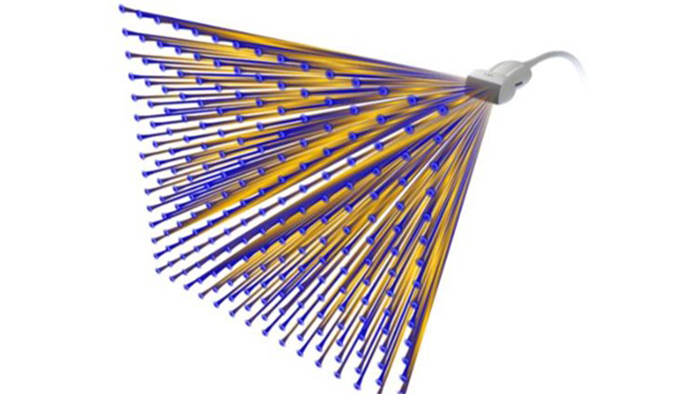

xMATRIX

La tecnología xMATRIX le permite ver con más claridad, realizar exploraciones más exhaustivas y decidir con más seguridad, lo que hará que las exploraciones resulten más sencillas y rápidas tanto para los profesionales sanitarios como para los pacientes.